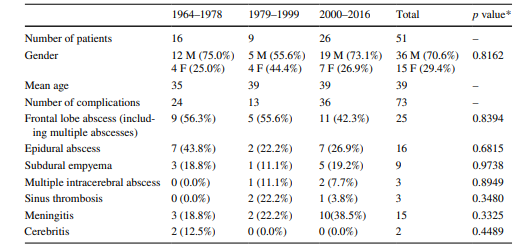

نتایج پنجاه و یک بیمار با عوارض داخل جمجمه ای سینوزیت از سال ۱۹۶۴ تا ۲۰۱۶ در این مطالعه وارد شدند. شرکت کنندگان از ۳۶ مرد و ۱۵ زن با میانگین سنی ۳۹ سال (یعنی محدوده ی سنی ۱۲ تا ۷۲ سال) تشکیل شده بودند. شیوع بیماری در بیماران با رده های سنی ۲۴-۲۵ سال بیشتر بود. جمعیت شرکت کننده در این مطالعه بسته به روش های درمانی متفاوتی که در طول دوره های زمانی ذکر شده ی قبلی ارائه شده، به ۳ گروه تقسیم شده بود: ۱۶ بیمار در دوره ی اول (۱۹۶۴–۱۹۷۸)، ۹ بیمار در دوره ی دوم (۱۹۷۹–۱۹۹۹) . ۲۶ بیمار در گروه آخر (۲۰۰۰-۲۰۱۶) قرار داشتند.

در ۲۵ بیمار، آبسه در سمت راست بود که شایع ترین عارضه ی یافت شده در تمام دورهها بود (۹ نفر در دوره ی اول، پنج مورد در دوره ی دوم و ۱۱ نفر در دوره ی سوم). تنها در یکی از بیماران مبتلا به آبسه ی لوب فرانتال چپ، آبسه های اپیدورال جمجمه و آمپیم ساب دورال وجود داشت. در بیمار دیگری، آبسه های فرانتال دو طرفه بودند. شانزده بیمار با آبسه ی اپیدورال (هفت، دو و هفت نفر به ترتیب در هر کدام از دوره های اول، دوم و آخر)، و نه بیمار با آمپیم ساب دورال (سه، یک و پنج نفر به ترتیب در هر کدام از دوره های اول، دوم و آخر) تشخیص داده شدند (شکل ۳).

در یکی از بیماران، چندین آبسه مغزی در لوب فرونتال و جداری مشاهده شد (شکل ۴). سه بیمار با ترومبوز سینوس علامت دار (۰، ۲ و ۱ در دوره های مربوطه) در کلینیک بستری شدند. دو بیمار سربریت داشتند. پانزده بیمار مبتلا به مننژیت بودند: هشت نفر با سبب شناسی استافیلوکوک یا استرپتوکوک و یک نفر هم با سبب شناسی ویروسی تشخیص داده شده. در دو بیمار، مایع مغزی نخاعی استریل بود (جدول ۲ و ۳).